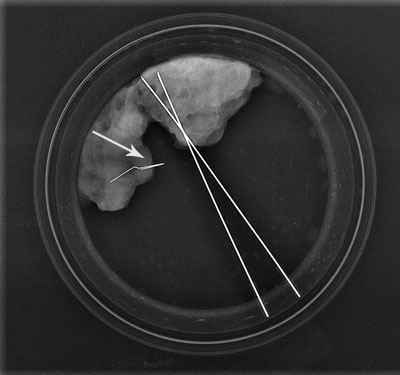

1 2 3

1 Repérage d'un clip post-biopsies 2 Repérage d'une masse 3 Contrôle per-opératoire de la pièce de tumorectomie (le repère est bien dans la zone d'exérèse)